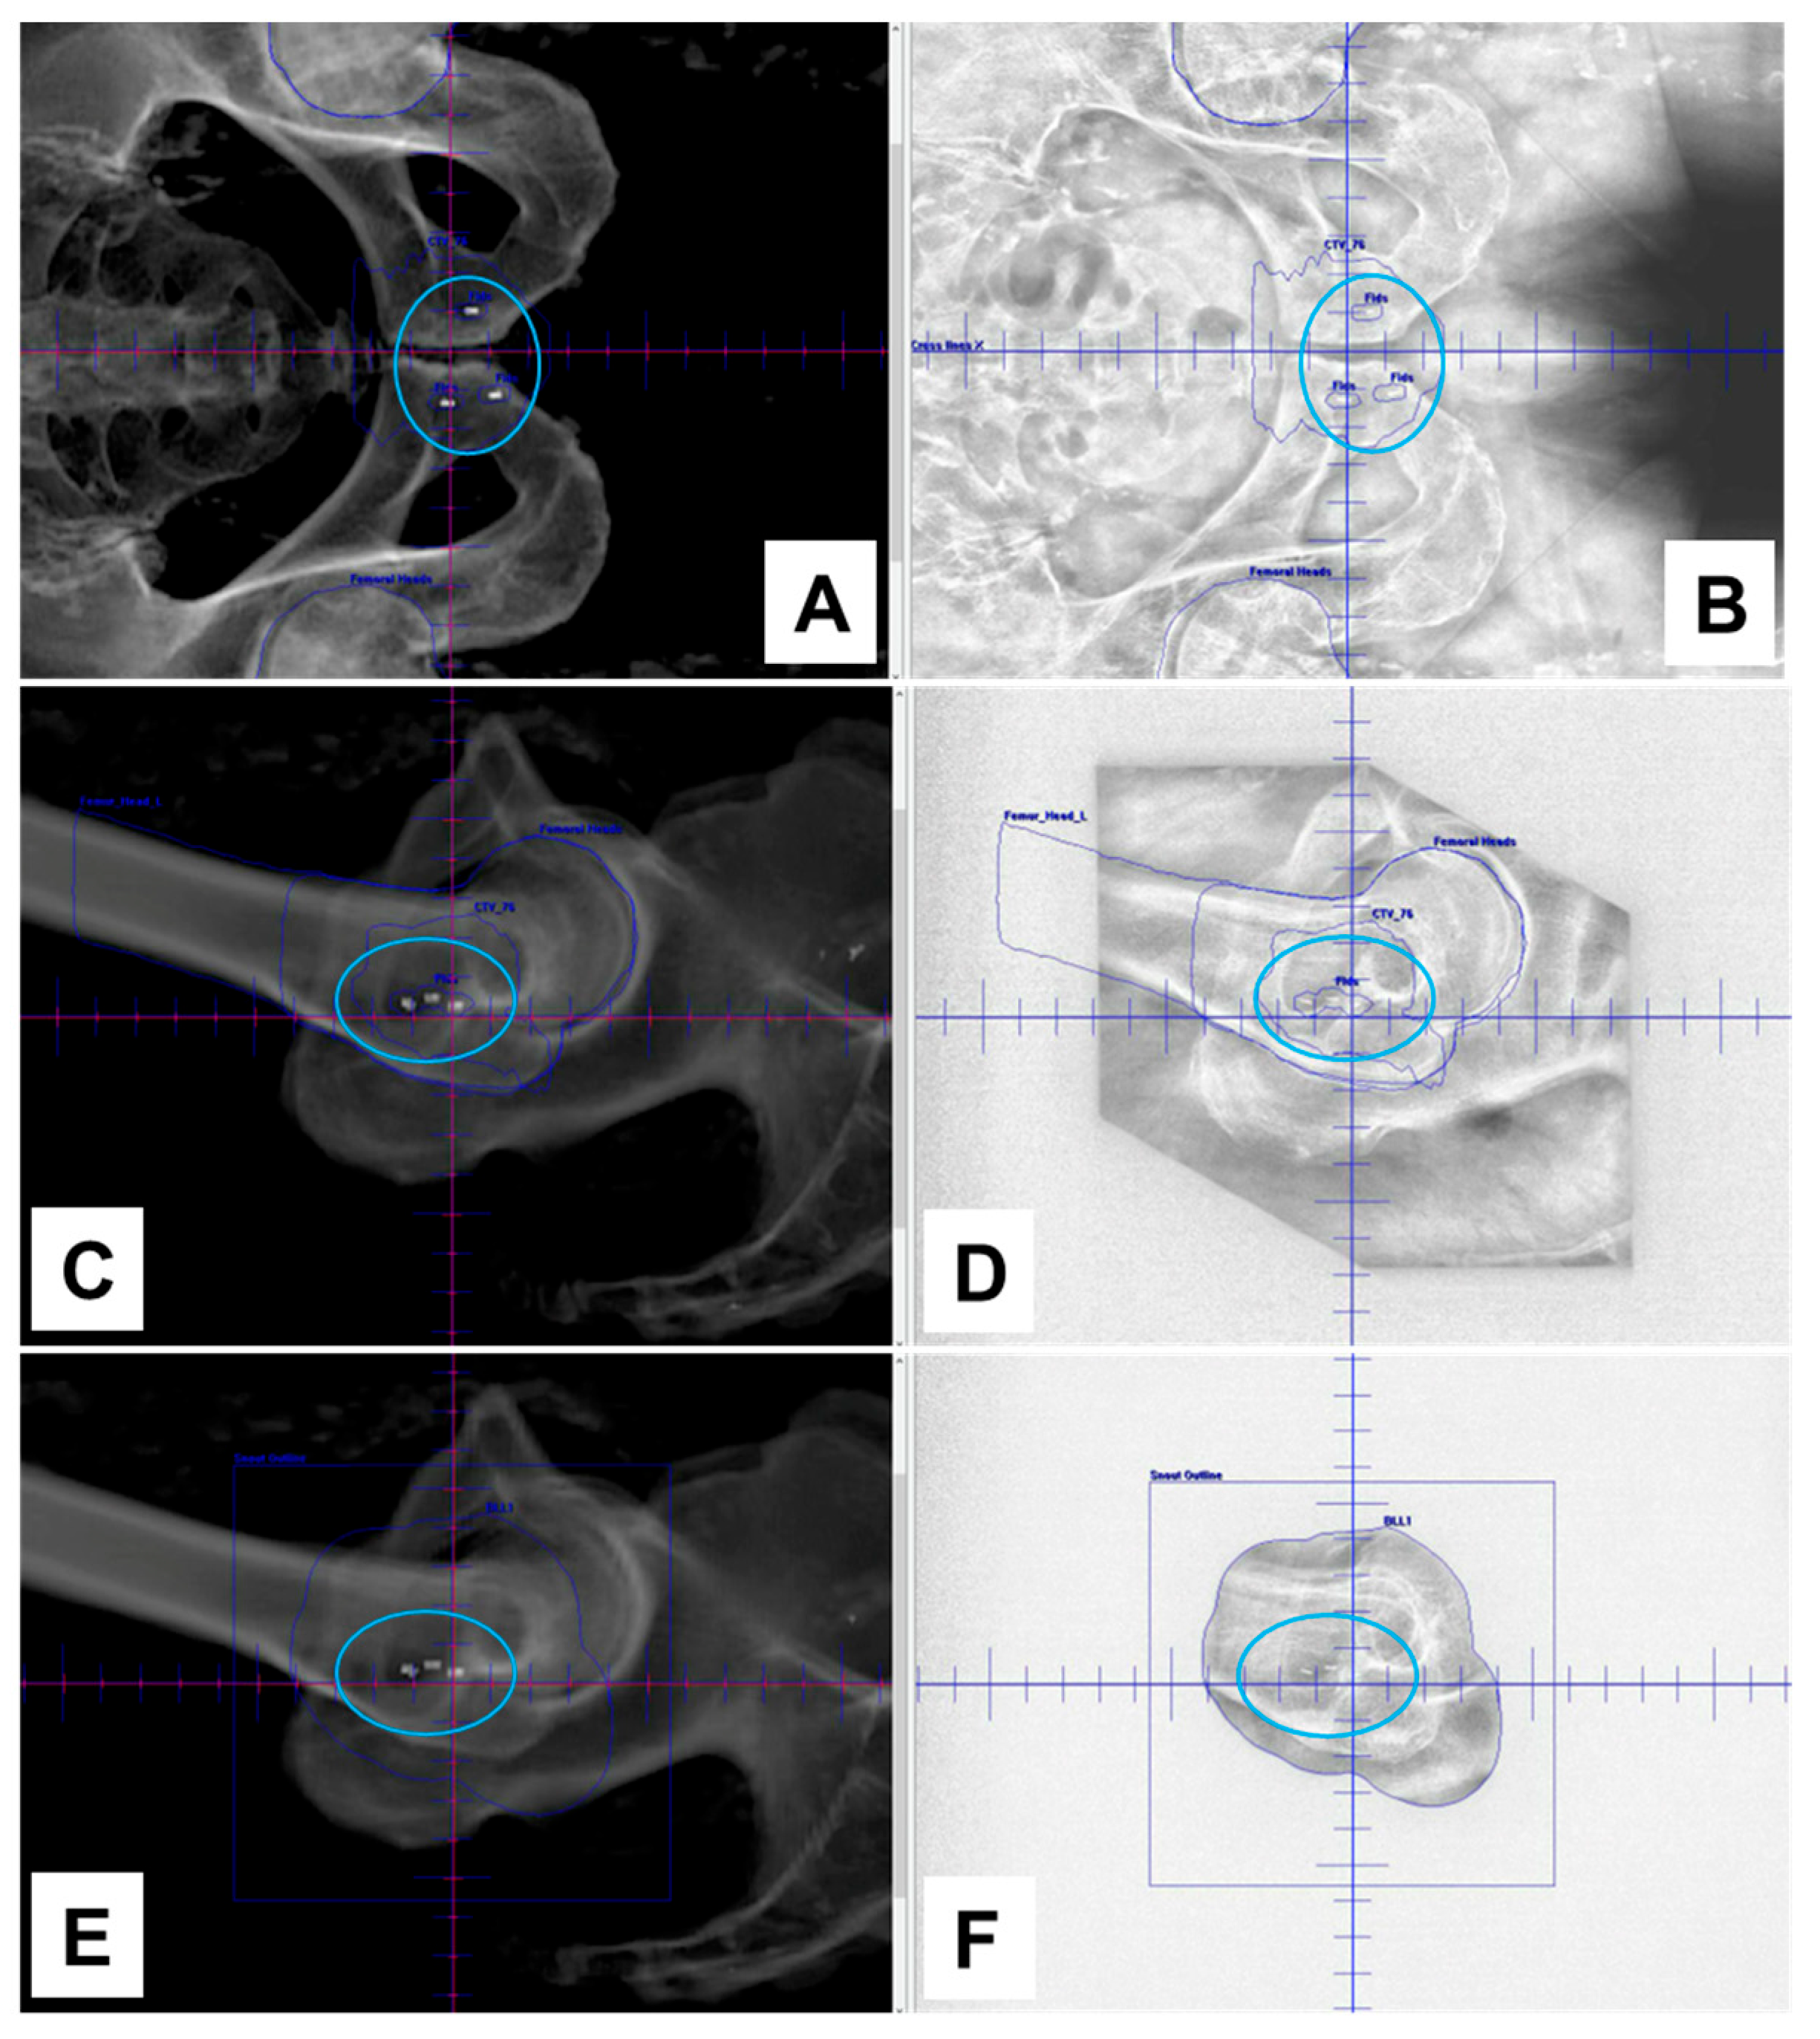

3.1. NOVA Marker Visibility in Phantom

3.2. NOVA Marker Artifacts on CT Images

3.4. Visibility of NOVA Markers in a Clinical Case